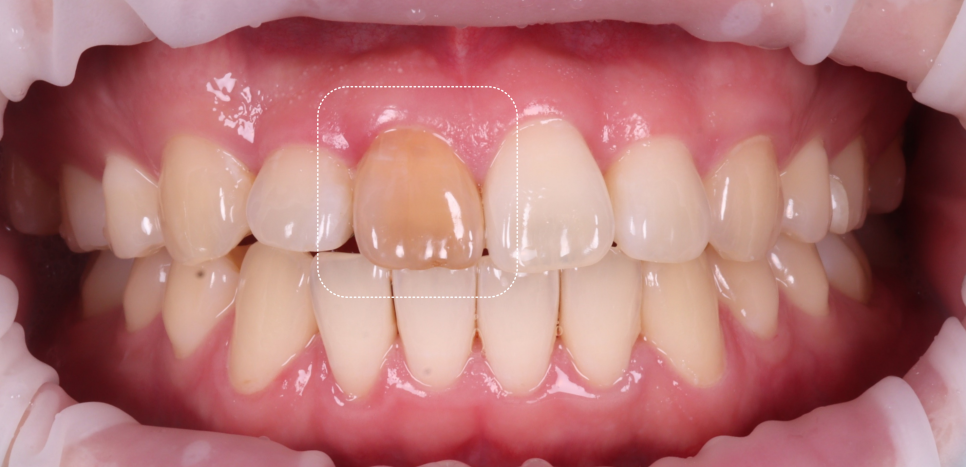

실활치 미백 가능하다고 판단했습니다.

확인해 보니 교정 후

해당 치아의 뿌리가 많이 흡수된

양상이 보였어요.

그렇지만 당장 빼기에는

너무 아까웠죠...

저도 최종적으로 레진 비니어를 통해

치료하기로 계획했지만,

그 전에 실활치 미백을 통해 바탕색을

미리 밝게 만들어야 한다고 진단했습니다.